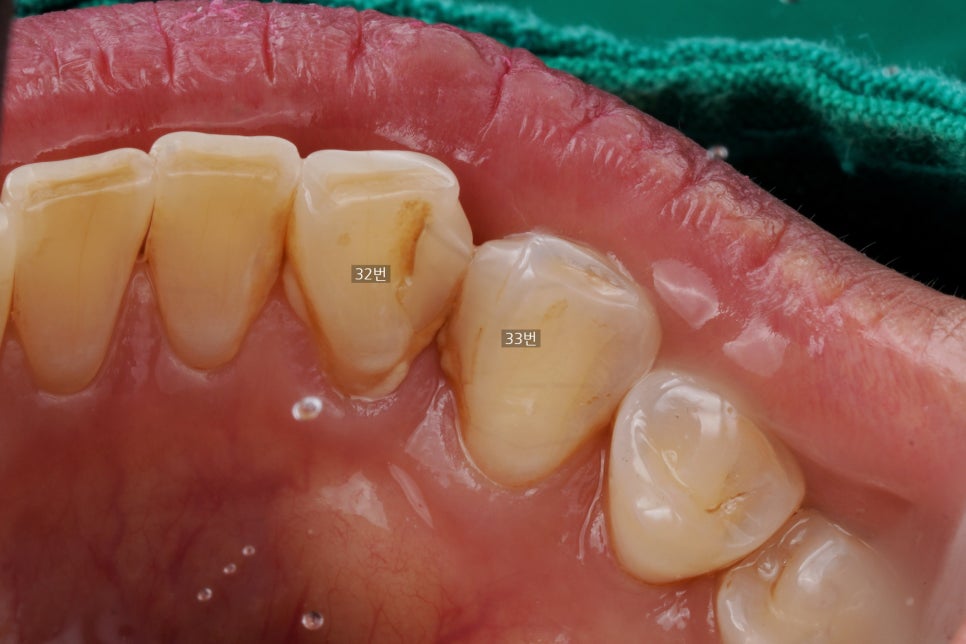

반대편 송곳니(33번치아)와 앞니(32번) 사이에도

예전에 때워놓은 레진 재료가 붙어있는데

이걸 마저 다 갈아내고

양쪽 송곳니를 레진으로 치료하는 거였습니다.

왜냐면 사진에서 보시다시피

옛날 레진이 다 마모가 되어있고

그 주변으로 변색도 있고

레진 하방으로 치석도 많이 쌓여 있어서

깨끗이 다시 치료하는 게

장점4. 장기적 잇몸 건강에도 좋다고 생각했기 때문입니다.